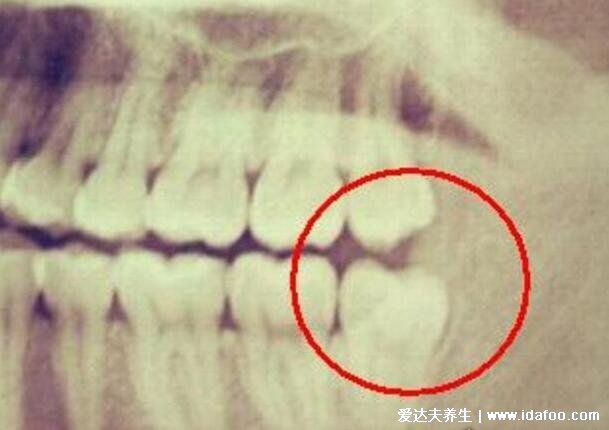

2、侵犯邻牙

这种自己不知道,需要在医院拍片来诊断,这种智齿萌生的空间不足,会倒在第二大臼齿上,导致牙齿不容易清洁,反复的诱发冠周炎,甚至还有部分牙齿被吸收的现象,容易造成神经痛、牙髓炎,必须拔!

阻生智齿就是会挤压到邻牙,长时间这样会把原本健康的牙都挤坏了,最终导致两颗牙齿都留不住。还有阻生齿如果是横生的智齿,那么非常难拔,要花的钱也更多,看史上最难拔的智齿图就知道了。